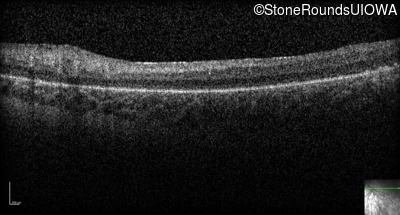

Optical Coherence Tomography - Right -

No Light Perception

Exemplar

Optical Coherence Tomography - Left -